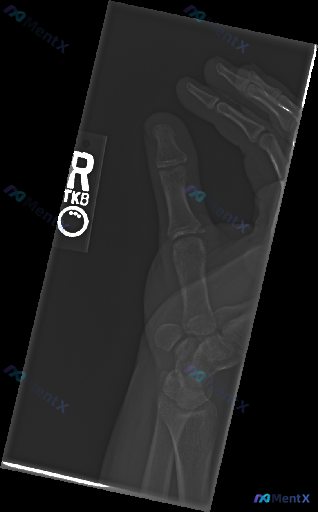

整理到一份右手拇指外伤的影像学资料,先放核心信息: - 影像:右手斜位X光片 - 主要发现:拇指近节指骨基底部骨皮质不连续,可见斜形透亮线,骨折线延伸至掌指关节面,有关节面台阶样改变,断端有轻度分离/移位倾向,周围软组织肿胀 - 暂未提供CT、病史及查体 仅从目前X光片来看,大家第一眼会更往哪个方向...